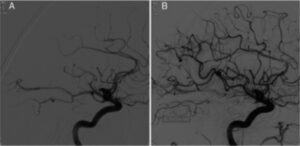

Thrombectomy for M2 occlusions

Thrombectomy for M2 occlusionsMany trials show that endovascular therapy (EVT) works to treat occlusions of the internal carotid artery or the M1 branch of the middle cerebral artery (MCA). AHA Guidelines suggest it might be reasonable to consider emergent EVT on more distal occlusions like M2 and M3 branch occlusions of the MCA. The Trevo Registry shows us that in real world practice, 23% of all thrombectomies are done for patents with M2 MCA occlusions. The figure shows restored blood flow in one such M2 occlusion before (A) and after (B) EVT.